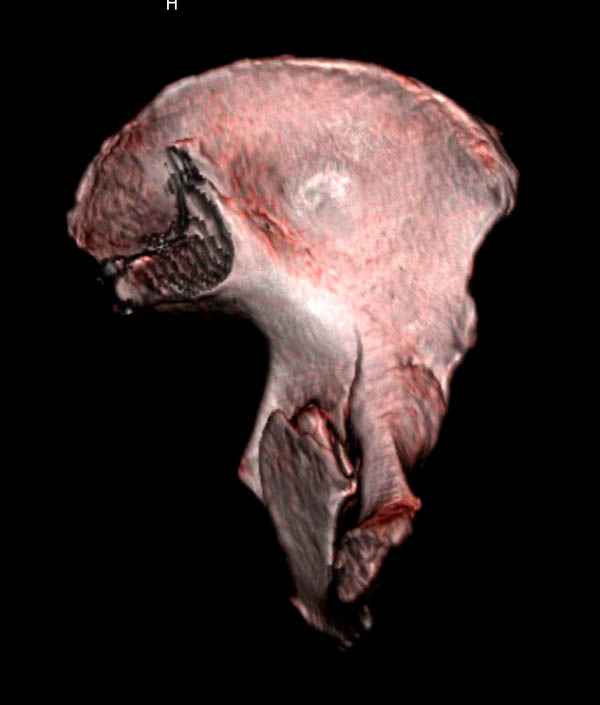

Уважаемые коллеги! С прошедшеми Вас праздниками. Теперь ближе к трудовым будням. Поступила 16 летняя девушка неделю назад. Механизм травмы падение с 5 этажа. Краткий диагноз:закрытый перелом левой ключицы, левого плеча, закрытый вертикально и ротационно нестабильный перелом костей таза:закрытый перелом левой подвздошной кости, переломы лонной кости справа, перелом обоих колонн вертлужной впадины слева;субкапитальный перелом шейки левой бедренной кости со смещением. По тактике лечения таза возникли следующие вопросы: 1. С чего начать - фиксации переломов вертлужной впадины или устранения деформаций таза? 2. Надо ли фиксировать шейку или фиксировать бедро в аппарате вместе с тазом, а после сращения таза планировать ТЭП ТБС? Если имеются еще какие подводные камни, будем рады выслушать.Спасибо.

На снимке ацетабулума редко встречающийся очень низкий перелом, наверное, трудно было репозицию через один доступ? Перелом как бы замкнулся в квадрилатеральной поврехности.